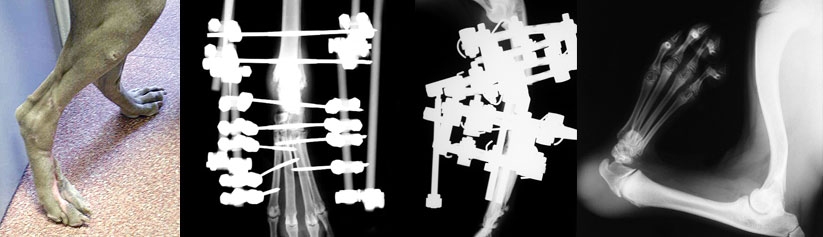

Case 2

A West Highland White Terrier pup with a deformed left forelimb. The paw is not connected to the radius which is the principle weight bearing bone in the forearm. As a result the paw is collapsing to the outside of the limb. A condition known as ‘ectrodactyly’.

X-ray and photograph of the same West Highland White Terrier as an adult dog, showing how the paw has been transposed from the ulnar bone and fused to the radius.

Case 3

This dog has a slow growing tumour affecting the radial bone just above the carpal joint (wrist) (arrows). The tumour has been removed and the gap packed with a bone graft and supported with two plates and multiple screws. It has been necessary to fuse the carpal joint.

The tumour has been removed and the gap packed with a bone graft and supported with two plates and multiple screws. It has been necessary to fuse the carpal joint.

Case 4

This cat has a benign tumour affecting the tibial bone just above the hock joint (ankle) (arrows).

The tumour has been removed and the gap filled with a metal (tantalum) prosthesis and supported with a specially designed curved plate. It has been necessary to fuse the hock joint.